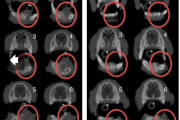

Aftoosne stomatiit

villikesest tekkinud haavand suu limaskestal